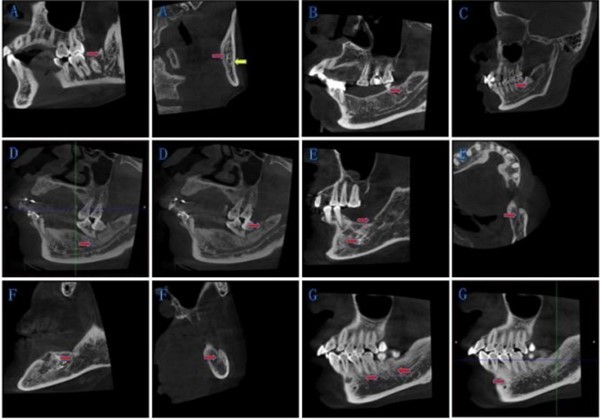

According to our rules, we divided BMC into four types. Type IA was bifurcations at the mandibular ramus, and retromolar foramen has been formed. Type IB was bifurcations at the mandibular ramus, and retromolar foramen has not been formed. We took those bifurcations at mandibular body as Type II. Type III was for bifurcations exist both at the mandibular body and the mandibular ramus on one side. Type IV for other circumstances. Details as following in Table 1 and Figure 2

*Note 1: If there are several branches at one side of the mandibular ramus at the same time,we add total numbers before the type and specific amount of subclass on the bottom right (e.g., 2IA, 3IA2B1). If the bifurcation point is exactly on the boundary of the body and ramus, we identify it as Type I.

*Note 2: If there are several branches, the number before the type represents the total amount, and the label at the top right shows the number of branches at the mandibular ramus; the label at the bottom right shows the number of branches at the mandibular body

Figure 2.New classification of BMC: The red arrow points to the bifurcations, and the yellow arrow points to the mandibular canal. (A) Type IA: Bifurcations at the mandibular ramus, and retromolar foramen has been formed. (B) Type IB: Bifurcations at the mandibular ramus, and retromolar foramen has not been formed. (C) Type II: Bifurcations at the mandibular body. (D)-(F) Type III: Bifurcations exist both at the mandibular body and the mandibular ramus on one side. (G) Type IV: Other circumstances.